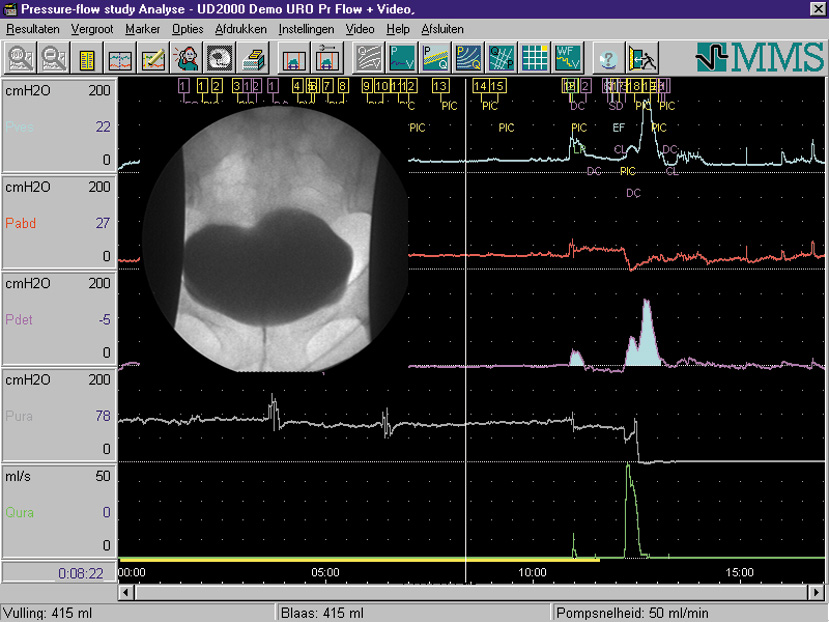

Είναι συνδυασμός πλήρους ουροδυναμικής μελέτης και ακτινολογικής διερεύνησης του ουροδόχου κύστης και της ουρήθρας.

Διενεργείται με την ταυτόχρονη χρησιμοποίηση του μηχανήματος ουροδυναμικής και ενός ειδικού ακτινολογικού μηχανήματος που λέγεται C arm.

Με αυτό τον τρόπο έχουμε ταυτόχρονη λήψη εικόνας και ουροδυναμικής μελέτης , πράγμα που ανεβάζει κατακόρυφα την διαγνωστική μας ικανότητα.